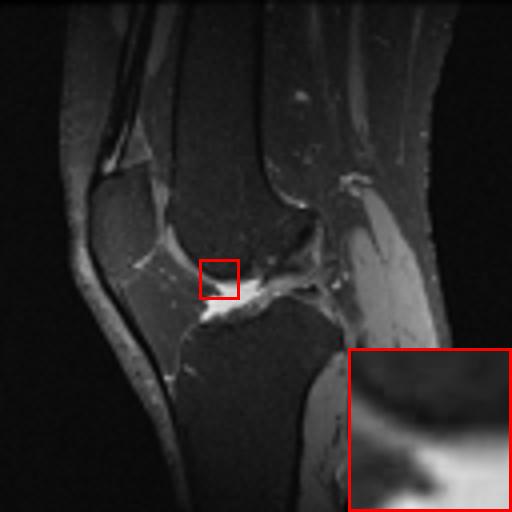

Figure 3: Reconstruction results of each algorithm for MRI images of the knee.

The PNSR/SSIM test results for the knee MRI test images for all contrast methods are shown in Table 1. The PNSR/SSIM test results for the abdominal MRI images are shown in Table 2. It’s worth noting that all metrics were calculated on cropped photos in order to eliminate the impact of non-subject areas. The quantitative results show that for knee MRI images, our proposed TT\mathrm{T}-GAN model achieves the best performance on the PSNR/SSIM metrics. For abdominal MRI images, our model essentially achieves optimal performance, with individual image WDSR slightly outperforming our model. The experimental results cousin that our model is more suitable for medical image super-resolution reconstruction than the existing deep learning-based image super-segmentation models.

We likewise give the visualization comparison results for each comparison algorithm, as shown in Fig. 3 and Fig. 4. It can be seen that the reconstructed images based on bicubic interpolation and deep learning based EDSR and WDSR both show oversmoothing phenomenon and some loss of detail information of the images. In contrast, our T-GAN performs better for the reconstruction of detail information due to the texture Transformer structure.